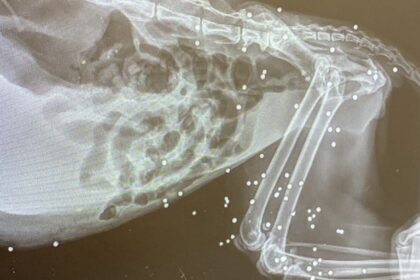

ANZIO | Sparano a una gatta di colonia, nel corpo trovati 77 pallini

Orrore e indignazione ad Anzio, dove una gatta appartenente a una colonia…